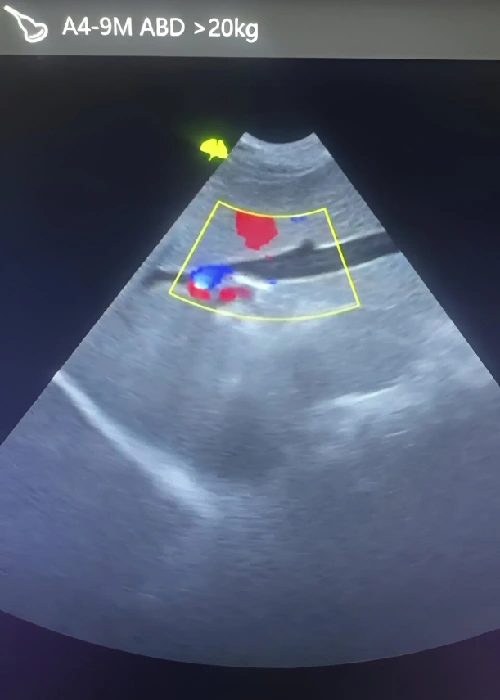

Ofrecemos servicio de ecografía veterinaria con equipos ecográficos modernos y personal capacitado para brindarte resultados confiables en poco tiempo.